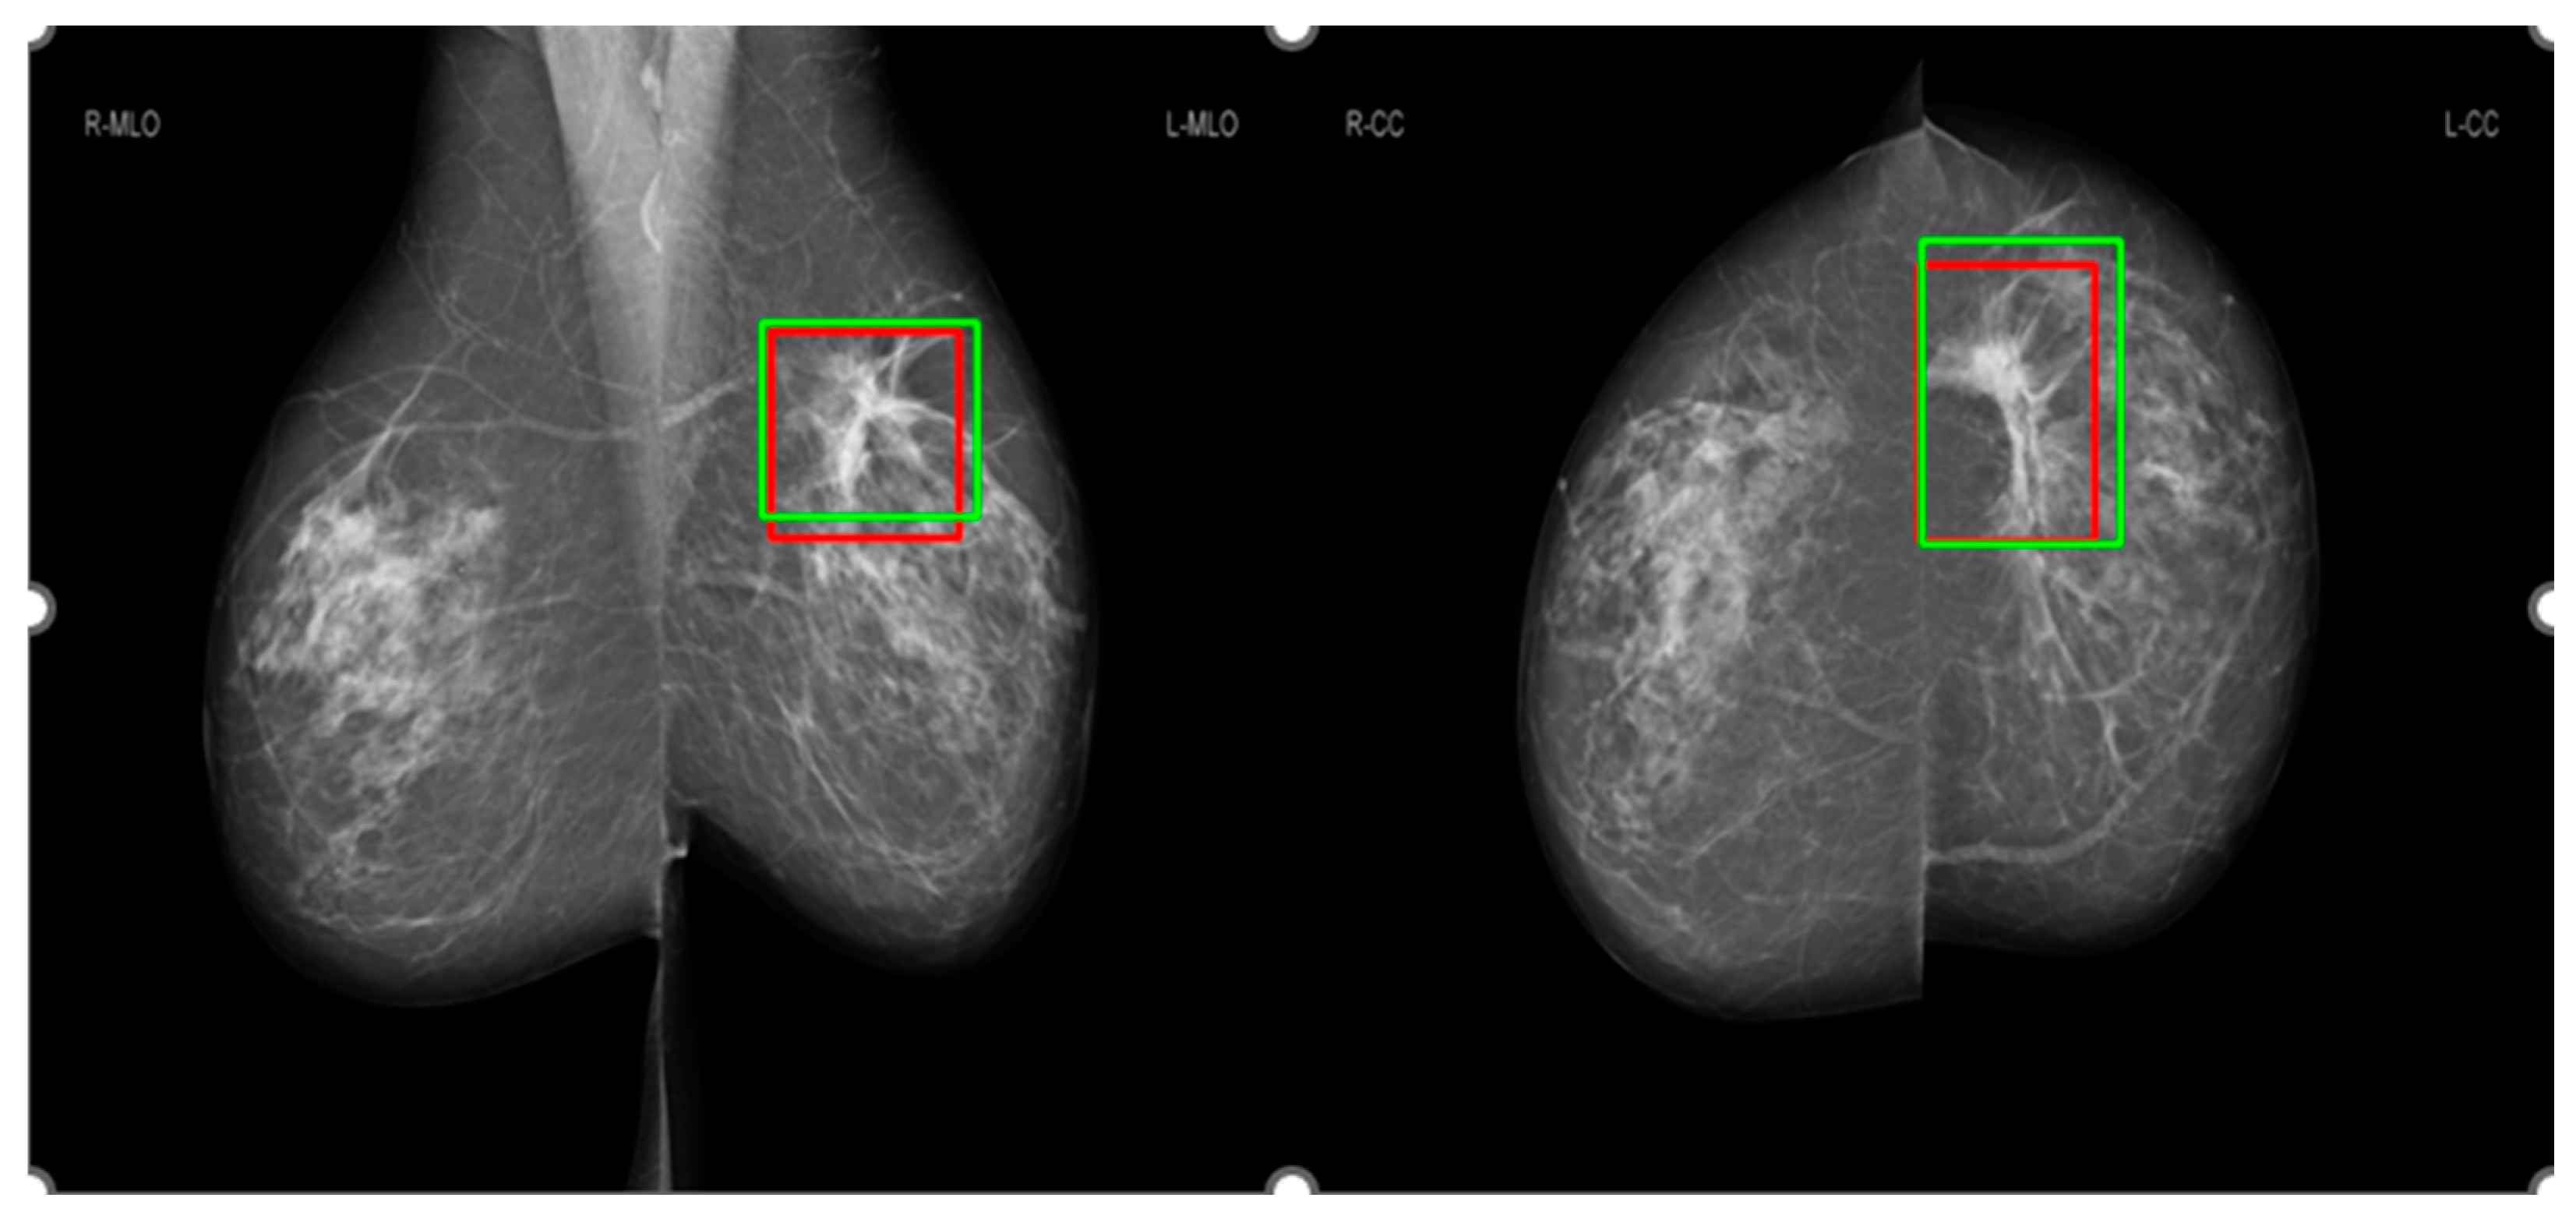

3.3. Comparison of salience maps on original and locally-enhanced mammographic images